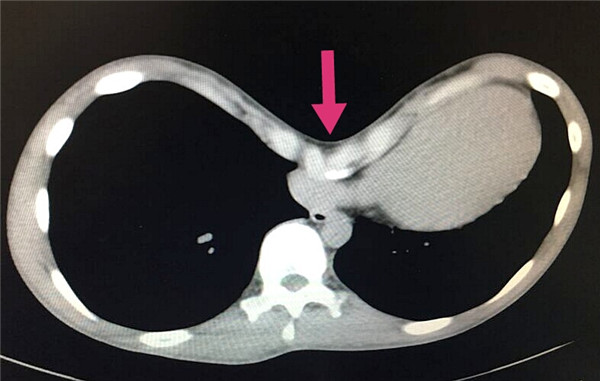

胸外科采用新技术成功治疗一名重度漏斗胸患者

近日,北医三院胸外科采用新技术成功治疗一名重度漏斗胸患者。经手术治疗后,患者严重胸壁畸形得到满意矫正,顺利康复出院。面对孩子重新挺起的胸膛,父母感激的心情溢于言表。 18岁的小康,因重度漏斗胸,历经辗转,...